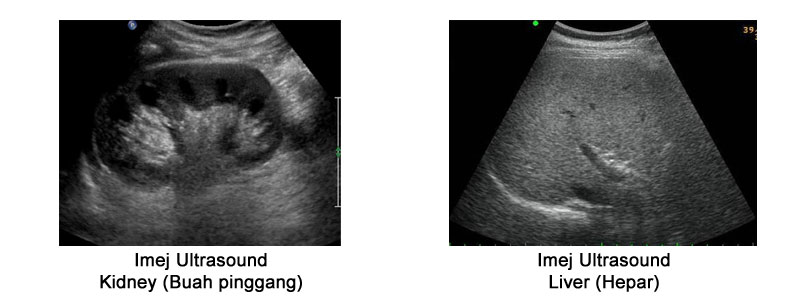

Ultrasound adalah sejenis pemeriksaan pengimejan menggunakan gelombang bunyi yang tinggi bagi menghasilkan imej yang terdapat di dalam tisu badan seseorang. Ia adalah pemeriksaan yang selamat kerana tidak menggunakan sinaran radiasi (x-ray ) dan sangat sesuai bagi pesakit terutamanya yang hamil. Unit ultrasound di tubuhkan pada Julai tahun 1997 sejajar dengan penubuhan HCTM.

Pemeriksaan yang ditawarkan di unit ini:

- Abdomen

- Hepatobiliary

- Urinary tract/ KUB